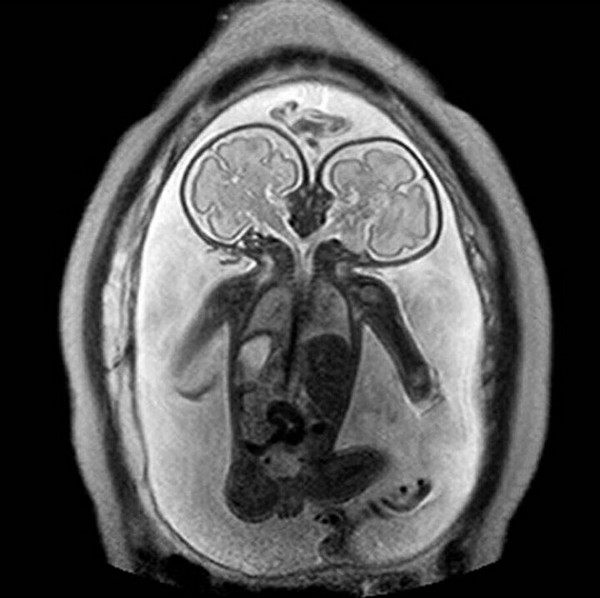

Обследование более 6 тысяч матерей и их новорожденных детей – являющееся одним из крупнейших исследований подобного рода – подкрепляет доказательства того, что курение сигарет во время беременности химически модифицирует ДНК плода, вызывая изменения, аналогичные наблюдаемым у взрослых курильщиков. Исследователи также обнаружили влияющий на развитие плода ген, подверженный негативному воздействию курения.

Предыдущие небольшие исследования находили связь между курением и химическими изменениями в ДНК или метилированием при развитии плода, но более глубокий анализ позволяет учёным раскрыть больше закономерностей. Международная группа исследователей собрала результаты обследования 6 тысяч 685 новорожденных и их матерей со всего света. На основании данных опросных листов матерей разделили по категориям на «постоянных курильщиц», которые ежедневно курили сигареты на протяжении большей части беременности (13 процентов), «некурящих» (62 процента) и тех, кто во время беременности «курил изредка» (25 процентов), к которым относились и те, кто бросил курить на ранних стадиях беременности.

Для анализа метилирования в ДНК новорожденных исследователи использовали образцы генов из крови, собранной, главным образом, из пуповины после родов. Для новорожденных, чьи матери попали в категорию «постоянных курильщиц», исследовательские группы выявили 6 тысяч 73 случая, когда ДНК была химически модифицирована иначе, чем у новорожденных с некурящими мамами. Около половины этих изменений могут быть привязаны к определённому гену.

Лондон и её коллеги обнаружили, что собранные образцы генов имеют отношение к развитию лёгких и нервной системы плода, а также к связанным с курением онкологическим заболеваниям и таким врождённым дефектам, как заячья губа и волчья пасть и другие. Отдельный анализ показал, что многие из этих модификаций ДНК проявлялись у детей более старшего возраста, чьи матери курили во время беременности.